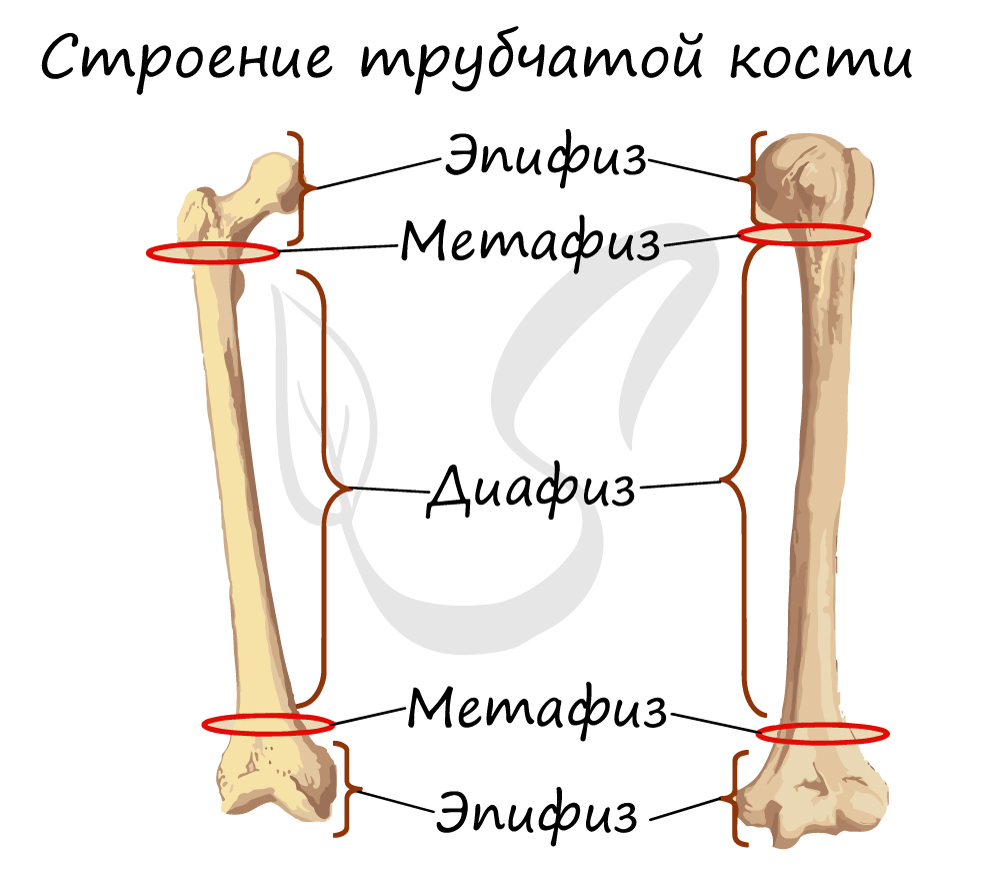

С точки зрения морфологии, размеры костей неодинаковы, их можно подразделить на длинные, короткие, плоские кости и кости неправильной формы. Длинные кости имеют форму трубки, средняя часть которых представляет собой диафиз, а оба конца – эпифиз. Эпифиз сравнительно толстый, имеет суставную поверхность, образованную вместе с соседними костями. Длинные кости главным образом располагаются на конечностях. Короткие кости имеют почти кубическую форму, чаще всего находятся в частях тела, испытывающих довольно значительное давление, и в то же время они должны быть подвижными, например, это кости запястья рук и кости предплюсны ног. Плоские кости имеют форму пластинок, они образуют стенки костных полостей и выполняют защитную роль для органов, находящихся внутри этих полостей, например, как кости черепа.

Кость состоит из костного вещества, костного мозга и надкостницы, а также имеет разветвленную сеть кровеносных сосудов и нервов, как показано на рисунке. Длинная бедренная кость состоит из диафиза и двух выпуклых эпифизарных концов. Поверхность каждого эпифизарного конца покрыта хрящом и образует гладкую суставную поверхность. Коэффициент трения в пространстве между хрящами в месте соединения сустава очень мал, он может быть ниже 0.0026. Это самый низкий известный показатель силы трения между твердыми телами, что позволяет хрящу и соседним костным тканям создать высокоэффективный сустав. Эпифизарная пластинка образована из кальцинированного хряща, соединенного с хрящом. Диафиз представляет собой полую кость, стенки которой образованы из плотной кости, которая является довольно толстой по всей ее длине и постепенно утончающейся к краям.

Строение трубчатой кости

Обратите свое особое внимание на то, что рост кости в длину осуществляется за счет эпифизарной пластинки. Именно за счет этой пластинки, располагающейся между метафизом и эпифизом, происходит рост кости в длину. Эпифизарная пластинка хорошо кровоснабжается.

Трубчатые кости, соответствуя своему названию, представляют собой продолговатое тело или диафиз и два утолщения на концах, эпифизы. Между эпифизом и диафизами расположены метафизы — зоны роста кости в длину. Метафизы постепенно заканчивают свою деятельность и постепенно окостеневают к возрасту полового созревания, когда рост тела в высоту останавливается. Этот период соответствует примерно 18 годам у девушек и 25 годам у парней. В современном мире существует понятие костного возраста, или истинного возраста, тела, в противовес календарному возрасту. Он определяется на основании стадии окостенения метафизов.